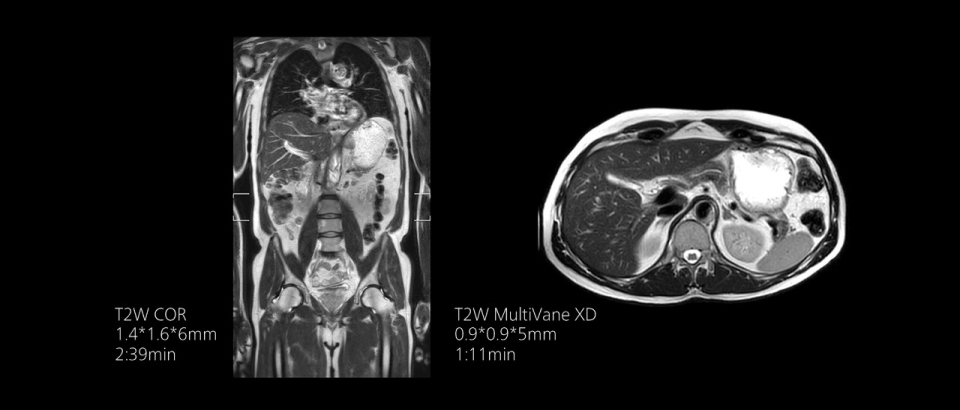

Compressed SENSEは、実質的に同等の画質を保ちつつ、撮像時間を最大50%²高速化します。

時間を味方につける - Compressed SENSEを使用すると、実質的に同等の画質を保ちつつ、撮像時間を最大50%²短縮できます。空間分解能が60%向上した高品質のMR画像を得ることで確実な診断が可能になります。